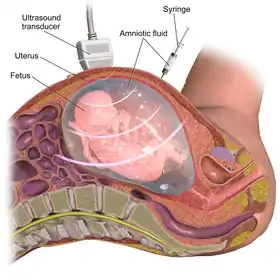

Amniocentesis

Amniocentesis is an invasive diagnostic test that can be done during the second trimester of pregnancy for individuals that are looking to identify or are at higher risk of passing chromosomal and/or neural tube abnormalities. The procedure is typically done via needle, in combination with ultrasound for guidance, to obtain a sample of the amniotic fluid surrounding the fetus.[51]

By invasiveness

| More invasive | Amniocentesis | This can be done once enough amniotic fluid has developed to sample. Cells from the fetus will be floating in this fluid, and can be separated and tested. Miscarriage risk of amniocentesis is commonly quoted as 0.06% (1:1600).[68] By amniocentesis it is also possible to cryopreserve amniotic stem cells.[69][70][71] | After 15 weeks |